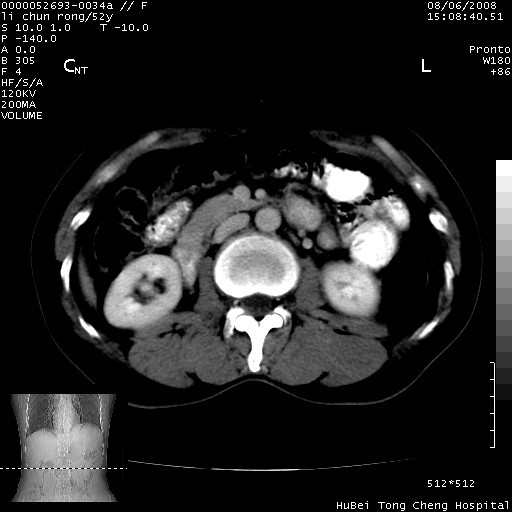

以下是引用云翔在2008-8-7 6:20:00的发言:[br]胰尾部囊性病变,考虑假囊肿,结合实验室检查疾病史

以下是引用zjzjr在2008-8-7 8:38:00的发言:[br]支持胰腺炎伴假囊肿形成,左肾小囊肿.少量腹水.

以下是引用随光逐影在2008-8-7 9:12:00的发言:[br]1)考虑胰腺炎伴假性囊肿形成可能性大;胰腺囊腺瘤待排。2)左肾小囊肿。3)少量腹水。